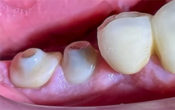

Comment devenir compétent en dentisterie esthétique ?

Les traitements esthétiques les plus complexes ne sont finalement qu’une succession d’actes plutôt simples… Restaurer sereinement un sourire, c’est d’abord en être l’architecte et établir un plan. C’est ensuite, en être le chef de chantier. Celui qui, applique avec rigueur des protocoles parfaitement définis et communique le maximum d’informations à son artisan, le prothésiste.